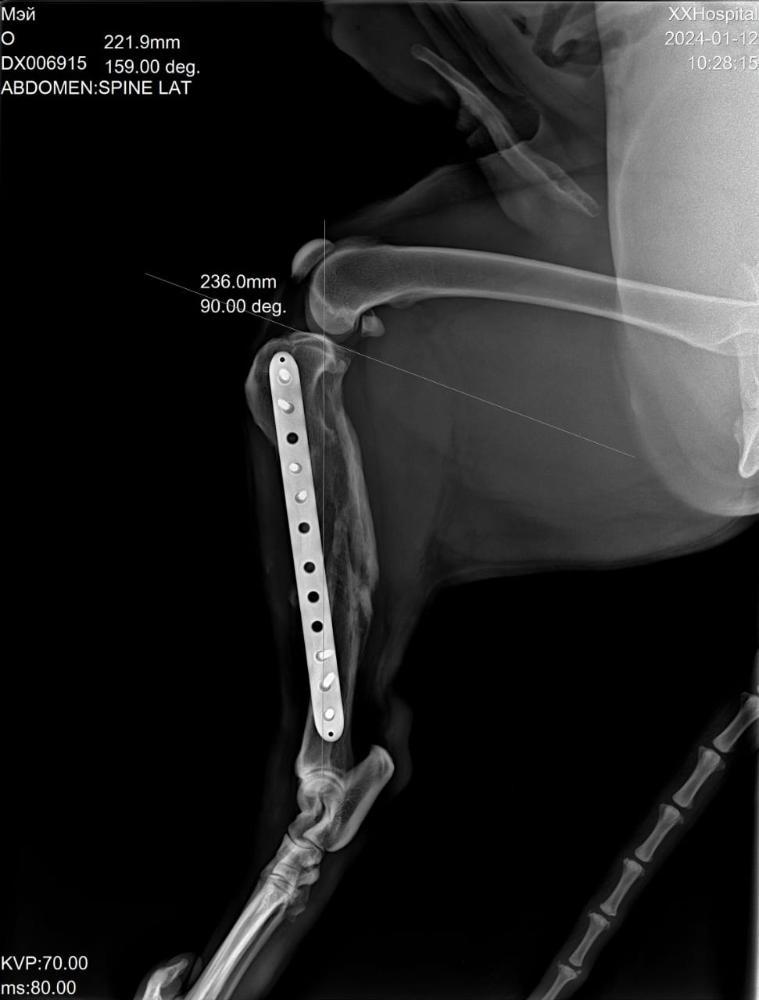

Светлана 2101 Опубликовано 12 января, 2024 Опубликовано 12 января, 2024 Сегодня съездили с Мэем к ортопеду. Сделали рентген. Сразу скажу, я осталась очень довольна приемом, содержательной беседой с врачом. Но есть новости хорошие и не очень. Сделано - рентген грудной и поясничный отдел, тазобедренных суставов и рентген оперированной лапы. По позвоночнику - в прекрасном состоянии, нет признаков травмы и дегенеративных изменений, кроме единичного незначимого очага дискоспондилита в среднем грудном отделе. На одном позвонке только есть изменения ( на снимке красным). Это ни о чем .Никак на жизнь не влияет. Тазобедренные суставы в отличном состоянии, без признаков дисплазии. В оперированной лапе - конструкция стабильна, признаки консолидации отломков. То есть всё хорошо. Доктор сказал, что далее ещё больше укрепляться будет. Процесс нарастания костной мозоли ещё идёт. Новости не очень. Измерил угол наклона плато, это крепление связок. Не очень владею всеми терминами, но своими словами напишу, как поняла. Этот угол у Мэя 20°, норма 14, при значении 25 и выше сто процентов разрыв ПКС неминуем. Хоть доктор и написал в заключении, что риск разрыва ПКС невелик, но на словах мне сказал, что вероятнее всего рано или поздно связки порвутся. 20° это уже большое натяжение, рвутся и при 22-23. Соответственно, рекомендации режим спокойных прогулок в монорежиме без кучных игр для минимизации нагрузки на коленные суставы . То есть спокойный режим даже не столько для оперированной лапы, сколько угроза разрыва ПКС. По словам доктора, это генетическая предрасположенность. В беседе он так сказал, что, да вы можете стараться его ограничивать от прыжков, но один раз он не прыгнет, а в другой раз всё равно прыгнет. Теперь вы знаете, что можно ожидать, но совсем собаку не ограничить во всем. А Мэй как раз очень прыгучий. Он даже на подзыв не просто подбегает, а прыгает.И бежит он прыжками. Один плюс, что он не знает диванов, и нет этого туда-сюда по 20 раз в день. Но на улице он хочет бегать. И бегает он очень мощно.Теперь понятно, что надо помнить об этом и стараться минимизировать прыжки . Но до сих пор связки целы, а прожил он с ними уже несколько лет, и режим у него был наверняка активный, никто его не ограничивал. Есть надежда, что продержатся они и ещё. И опять здесь очень хорошо, что он на НП, натуральные коллагены и Хондроитины помогут укреплению связок и сохранят суставы и позвоночник ,которые сейчас в прекрасном состоянии . Вот такое обследование. Я очень рада, что нет проблем в позвоночнике и суставах. Но не без ложки дегтя. Всё равно спокойный режим прогулок и жизни. А там как сложится. Просто теперь мы об этом знаем, что можно ожидать . 4 3

Светлана 2101 Опубликовано 12 января, 2024 Опубликовано 12 января, 2024 Рентген грудного отдела, вот единственный позвонок с дискоспондилитом, остальные все красивые Рентген пояснично крестцового отдела. Без изменений. Рентген тазобедренные. Рентген конструкции на оперированной лапе и углы. 5